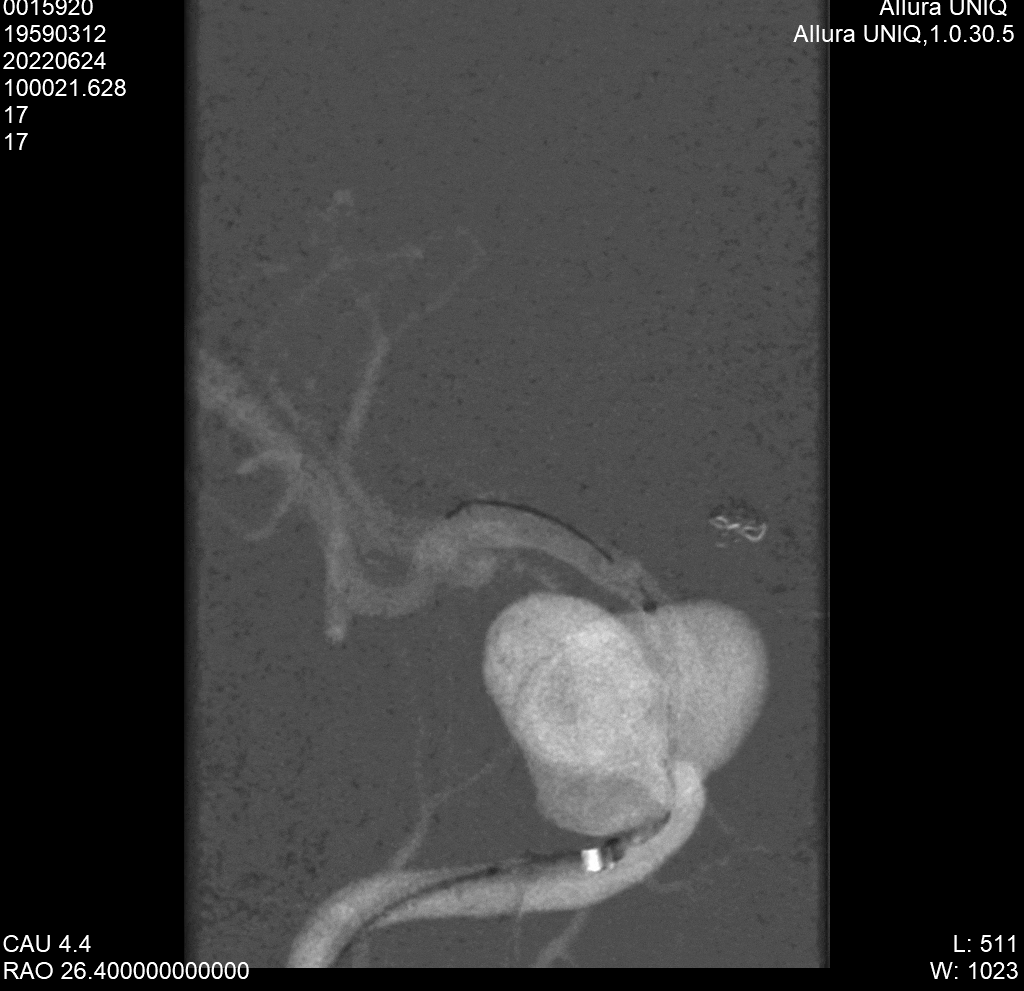

术中双侧股动脉穿刺置鞘。经右侧8F鞘6F 90cm长鞘置于颈动脉起始部,然后再将5F 105 Tethys中间导管放置于瘤颈近端建立稳定通路,XT-27超选至大脑中M1。经左侧6F鞘将Enchlon经造影管超选至瘤腔备用。

YonFlow 3.25mmx25mm支架在预定位置打开锚定。

边释放支架,边“推拉”支架,促进其打开,覆盖瘤颈。

支架全部打开,定位满意,释放开关,解脱支架。